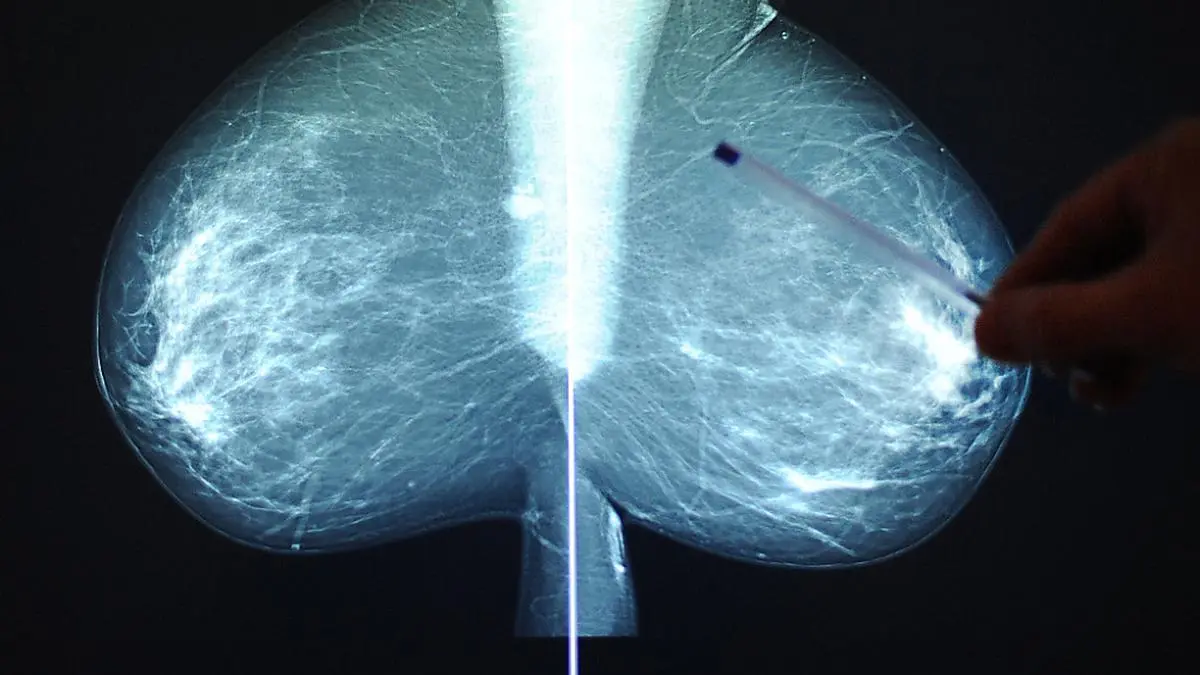

KI verbessert Versorgung von Brustkrebspatientinnen

Computer-Programme, die unter Künstlicher Intelligenz subsummiert werden, verändern auch die Medizin. Für Frauen soll das eine deutliche Verbesserung der Versorgung in Sachen Brustkrebs bringen, erklärte aus Anlass der bevorstehenden Internationalen St. Gallen Brustkrebskonferenz die Wiener Radioonkologin Daniela Kauer-Dorner.